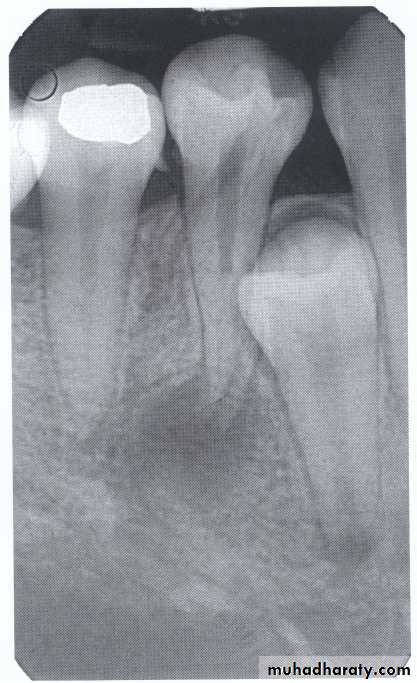

specimenX-Ray

Dilacerated root. The apical portion of the root is bent buccally or lingually into the plane of the central ray. Note the halo in the apical region, produced by the PDL

space (arrow).